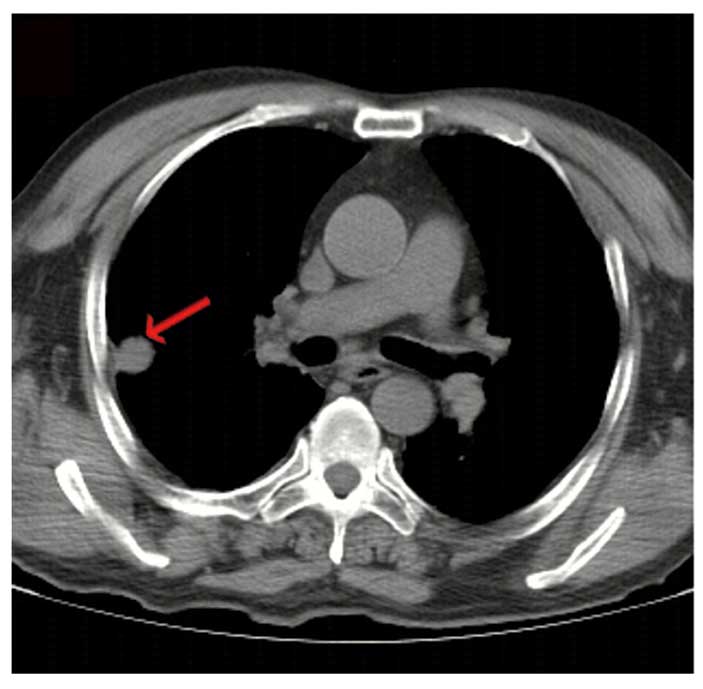

Figure 3.

Computed tomography (CT) images. The initial chest CT revealed a mass of ~1.6 cm located in the right lung (arrow).

A neurological examination revealed proximal muscle weakness and absence of deep tendon reflexes. The cranial nerve, cerebellar and sensory functions were all normal. The laboratory tests revealed hyponatremia and hypochloremia. The electromyogram suggested neurogenic damage (Bilateral abductor muscle and peroneus longus, potential loss of the median nerve, the common peroneal nerve, and mild slowing of the motor conduction velocity of the tibial nerve). A repetitive nerve stimulation test performed on the right median nerve revealed a decremental response to the electrical stimulation. An experiment with neostigmine supported the presence of postsynaptic membrane lesions. Repeated nerve stimulation of 7 Hz lead to an increased response, whereas repeated nerve stimulation of 15 Hz was associated with decreased response (Fig. 1). The findings of magnetic resonance imaging scans of the brain and lumbar vertebra were normal. The preliminary diagnosis of the patient's condition was MG. However, treatment with hypertonic saline and fluid restriction, as well as low-dose corticosteroid therapy for MG, did not improve the symptoms. After referring to several studies in the literature (6–8), LEMS was taken into consideration. The levels of tumor markers, including carcinoembryonic antigen and neuron-specific enolase, were found to be abnormal. An ultrasound of the superficial lymph nodes identified an enlarged lymph node in the right cervical region, sized 1.5×0.9 cm (Fig. 2). Chest computed tomography (CT) images revealed a 1.6-cm mass in the superior lobe of the right lung, associated with a small amount of pleural effusion (Fig. 3). A right cervical lymph node biopsy was conducted; on pathological immunohistochemical examination, the lesion was found to be positive for epithelial membrane antigen (+), CD56 (+), thyroid transcription factor-1 (+), creatine phosphokinase (+) and Ki67 (+++) and negative for synaptophysin and leukocyte common antigen. Combined with the findings of the histopathological analysis (hematoxylin and eosin staining; Fig. 4), the diagnosis was eventually confirmed as SCLC combined with LEMS.